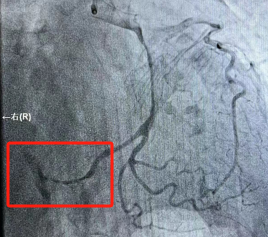

1697763870661024.jpg

回旋支远端完全闭塞

此时,患者的胸痛症状丝毫没有缓解,复查心电图显示下壁导联ST段仍持续抬高。患者病情刻不容缓,经过短暂思考后,熊主任当机立断:尝试开通回旋支远端血管!在熊主任的指导下,刘燃医师小心翼翼的置入预扩球囊扩张回旋支远端,果然发现左旋支直径2.5mm,是右心供血功能血管。但是血管扩张后患者突然出现心率减慢、血压降低的现象,面对这种突发状况,熊主任考虑患者是再灌注后血管痉挛、心律失常,刘医生立即向冠脉内注射硝酸甘油200μg,随后患者心率、血压回升到正常。在进行重复造影后可见患者回旋支远段粗大且长,延伸至右心,再次确定回旋支远端为“罪犯血管”。经过球囊扩张手术后,血管狭窄解除,血流3级,心电图提示下壁导联明显回落,胸痛症状明显缓解,手术有效,抢救成功!